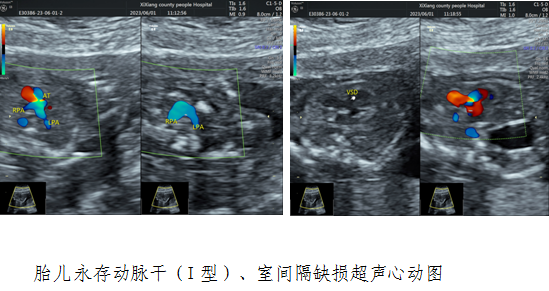

病例三,38岁,孕17w+4,G4P1,产前无创DNA筛查结果显示高风险(21三体检测值12.14)。贾玄慧医生对胎儿进行了全面超声检查,结合遗传学检查,结果显示胎儿心脏存在严重畸形—胎儿永存动脉干(I型)和室间隔缺损,告知孕妇疾病预后差,胎儿存活可能性低。孕妇于外院复查结果一致终止妊娠,最大程度降低妊娠风险。